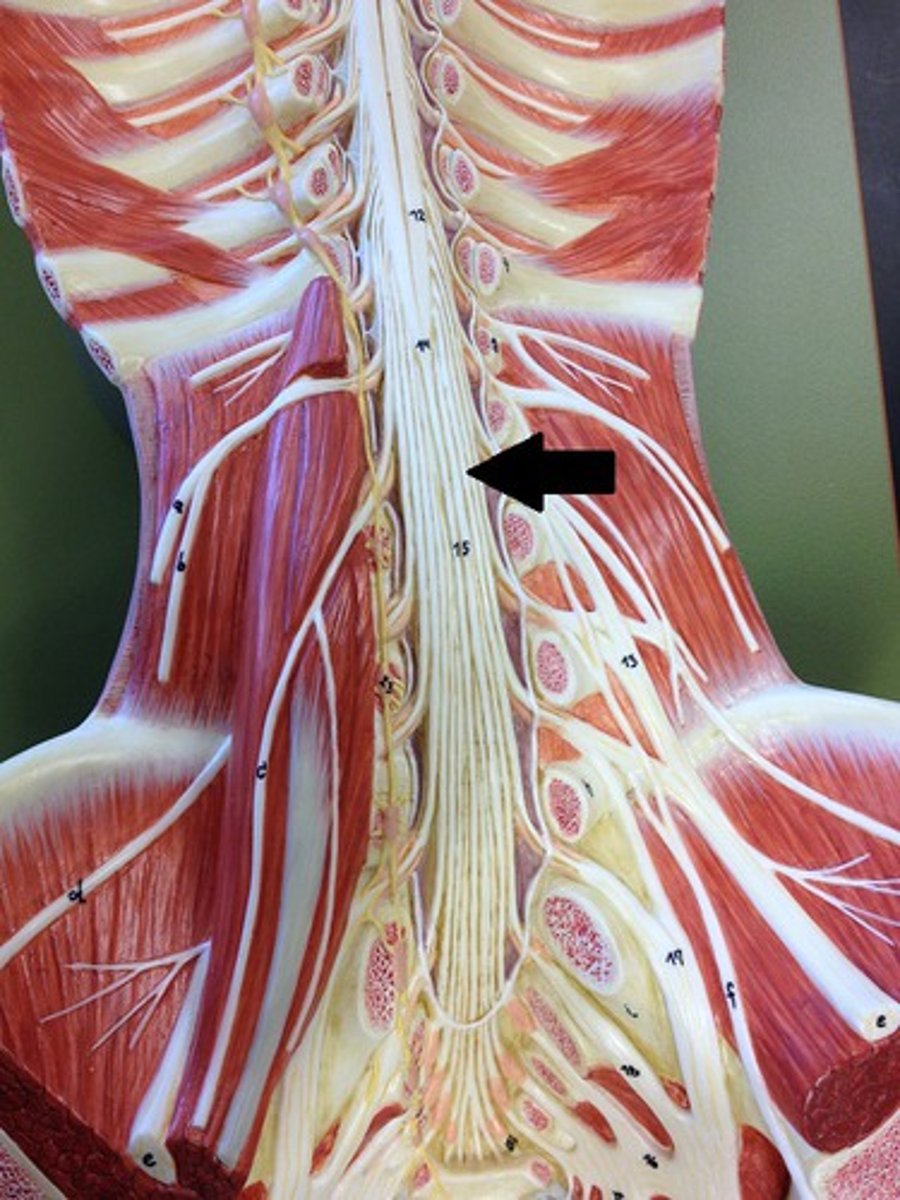

filum terminale

single thin thread of fibrous tissue at end of conus medullaris in the center that attaches to coccygeal ligament

posterior root

axons of sensory neurons

posterior root ganglion

anterior root

axons of motor neurons

spinal nerve

cauda equina

bundle